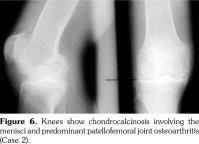

On examination, there was swelling and painful restriction of movement in her right knee. Imaging revealed calcification of cartilage of wrists, knee joints and hip joints although no microscopic confirmation was possible at this stage (Figure 1-4). She was investigated for a possible cause for CC, although investigations to screen for a metabolic cause turned out to be negative with a possibility for hereditary CC.

His hand X-rays showed hook like projections arising from radial aspect of second and third metacarpal heads with scapholunate advanced collapse and indentation of distal radius by the scaphoid bone. It also showed CC of the triangular fibrocartilage (Figure 6).